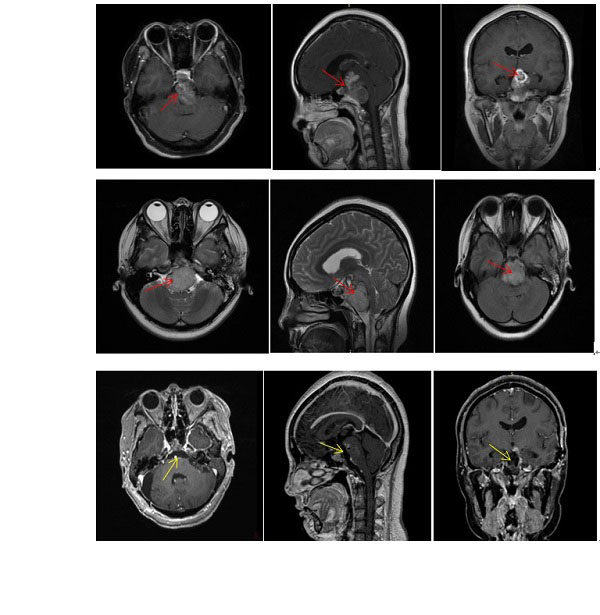

不出所望,雯雯较终的脊索瘤切除率达到了95%以上,并且手术后顺利的出院,恢复状态良并且生活质量等到了好转,有了更多生存希望。

从雯雯的手术前后对比影像中,我们就可以见证巴特朗菲教授高超的手术技术能力。除了在脊索瘤治疗领域方面精通,巴特朗菲教授还擅长治疗胶质瘤、海绵状血管瘤以及室管膜瘤等多种肿瘤的治疗,在颅底手术、大脑和脊髓血管病变显微手术方面做出了贡献。目前,他不仅是德国汉诺威国际神经科学研究所(INI)神经外科教授和血管神经外科中心主任,还是国际神经外科联合会(WFNS)教育委员会现任主席以及欧洲神经外科杂志Neurosurgical Review主编。